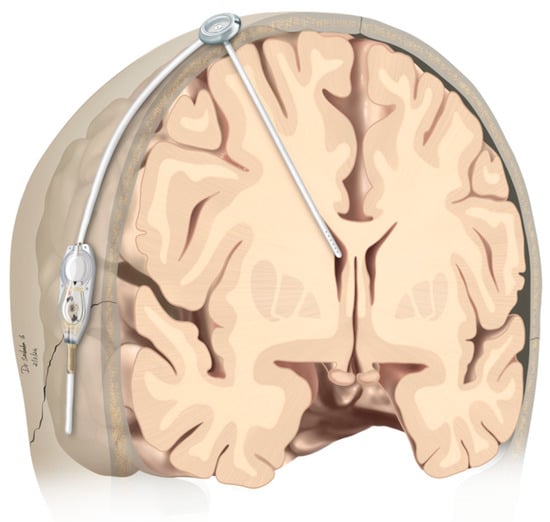

2.2. Operative Procedure

3.4. Feasibility/Procedure of ITC with mS/R